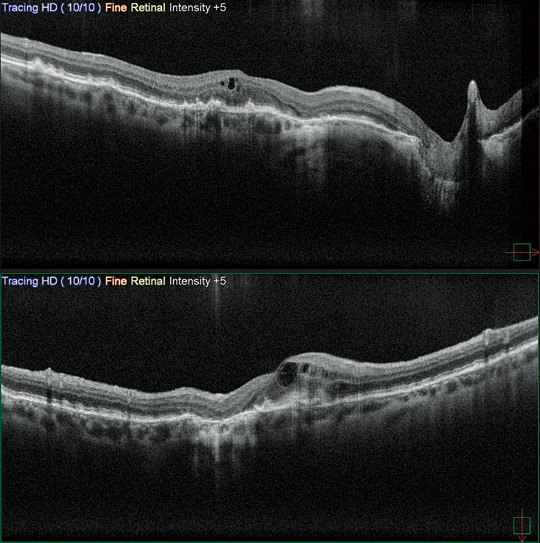

高清廣域OCT*

Mirante的掃描區域可達16.5 x 12毫米,單次拍攝就可實現包括黃斑和視盤的廣域診斷。超精細模式和高清自動追蹤功能可提供從玻璃體到脈絡膜的高質量圖像來觀察細微的病理改變。

黃斑線掃16.5毫米/2,048次A掃描